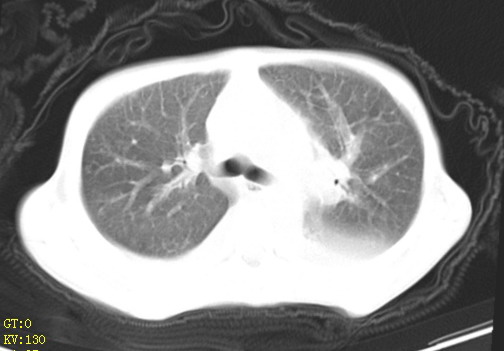

女,12岁,气促、咳嗽2天,3个月前查胸片示:两肺感染,急诊入院查ct,血常规等未检查。

1、左心房、左心室增大,考虑左心衰, 2、肺水肿合并感染 3、双侧胸腔积液

双肺中下野不规则片絮状阴影,中外带明显,双侧胸腔少量积液,心影增大,心腔密度减低,隆突下及左侧气管旁见钙化淋巴结影,考虑双肺感染、心衰;建议结合临床除外h1n1并急性心衰,先心不能排除。

两肺多发片絮状模糊影,以下肺外带居多,内见支气管气像,纵膈窗未减影,两侧胸腔积液,心影增大,结合心超,支持重症肺炎,非常时期,甲型h1n1流感不排除。